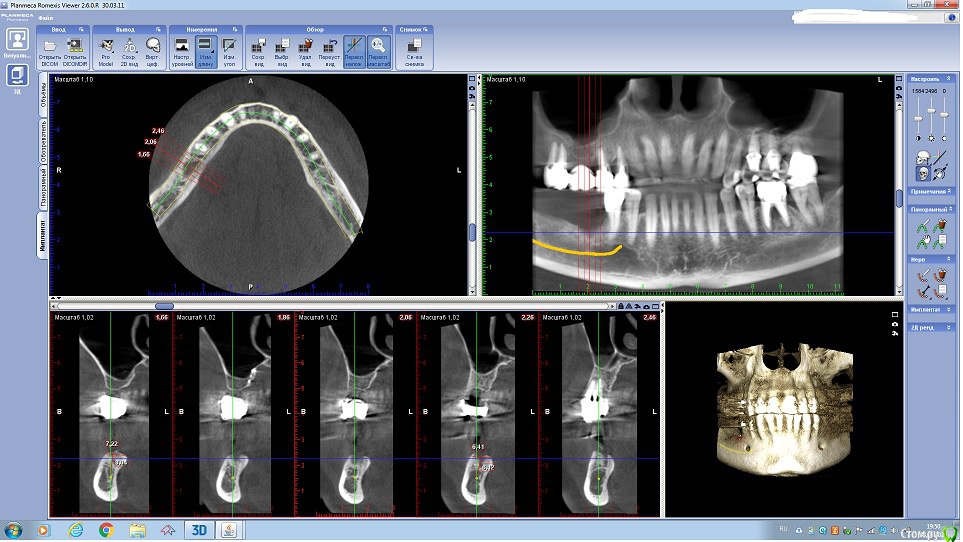

Fin Опубликовано 29 июля, 2020 Поделиться Опубликовано 29 июля, 2020 Здравствуйте коллеги. У пациента отсутствуют зуб 3.5 и 3.6. и высоко расположенный канал тройничного нерва. Что бы вы сделали в данном случае? Наращивать ширину? Ставить ССТ? Ссылка на комментарий

annda Опубликовано 3 августа, 2020 Поделиться Опубликовано 3 августа, 2020 (изменено) Стоял до этих имплантатов суперлайн коротыш 7мм,одиночка.Заколебались с раскруткой винта,ходила каждый месяц.Плюнула,решили выкрутить,переставить на эти.КТ после удаления. Изменено 3 августа, 2020 пользователем annda 1 Ссылка на комментарий

annda Опубликовано 4 августа, 2020 Поделиться Опубликовано 4 августа, 2020 Что-то с загрузкой пошло не так,извините.Контроль после постановки и контроль с абатментами(через 3 месяца) Ссылка на комментарий